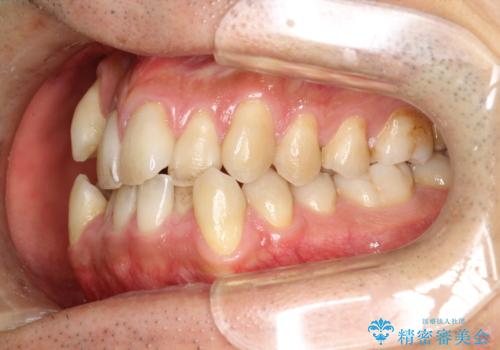

ガタガタの歯並び、八重歯をなおしたい、骨格性下顎前突 カモフラージュ矯正

患者様にはかなり満足していただける結果となりました。

八重歯(3番)などは歯肉移植も検討できればよいかなと思います。